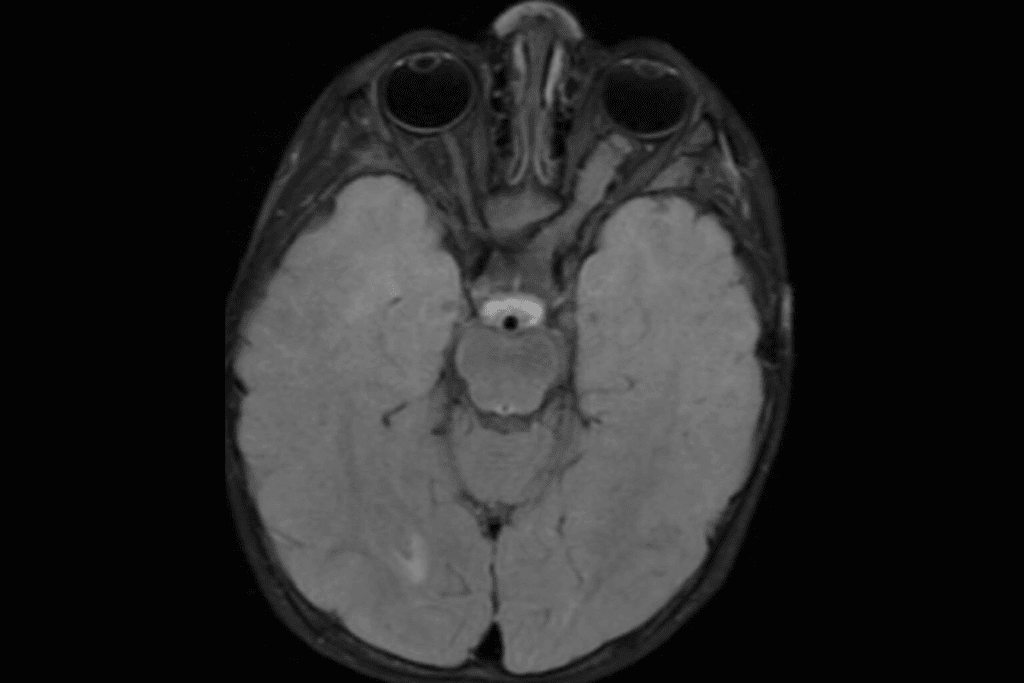

The human nervous system is the most complex network in the known universe, controlling everything from your heartbeat to your memories. Neurology is the medical branch dedicated to preserving this intricate system. At Liv Hospital, our Neurology Department serves as a regional center of excellence, combining the diagnostic precision of experienced clinicians with next-generation technology like 3 Tesla MRI and Video-EEG monitoring.

• Advanced Diagnostics: We utilize 3 Tesla MRI for ultra-high-resolution brain imaging and Video-EEG monitoring units for precise epilepsy characterization.

Doctors use advanced imaging tools such as 3 Tesla MRI, CT, and PET scans to visualize the brain’s structure. They also use tests like EEG to assess brain activity and EMG to assess nerve and muscle function. These help find the exact problem.